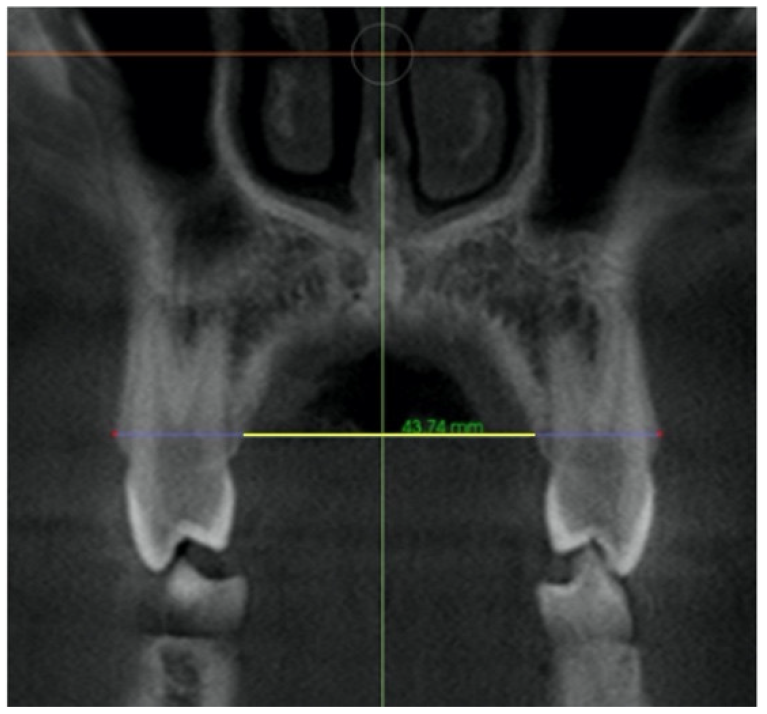

| Nasal Floor (NF) | Distance from right and left external edges of the palatine suture at the level of the nasal floor in the coronal view. On a coronal cross-sectional slice through the center of the first molar. The suture external edges were verified in the axial cross-sectional slice. | ![]() |

| Palatal Floor (PF) | Distance from right and left external edges of the palatine suture at the level of the palatal floor. On a coronal cross-sectional slice through the center of the first molar. The suture external edges were verified in the axial cross-sectional slice. | ![]() |